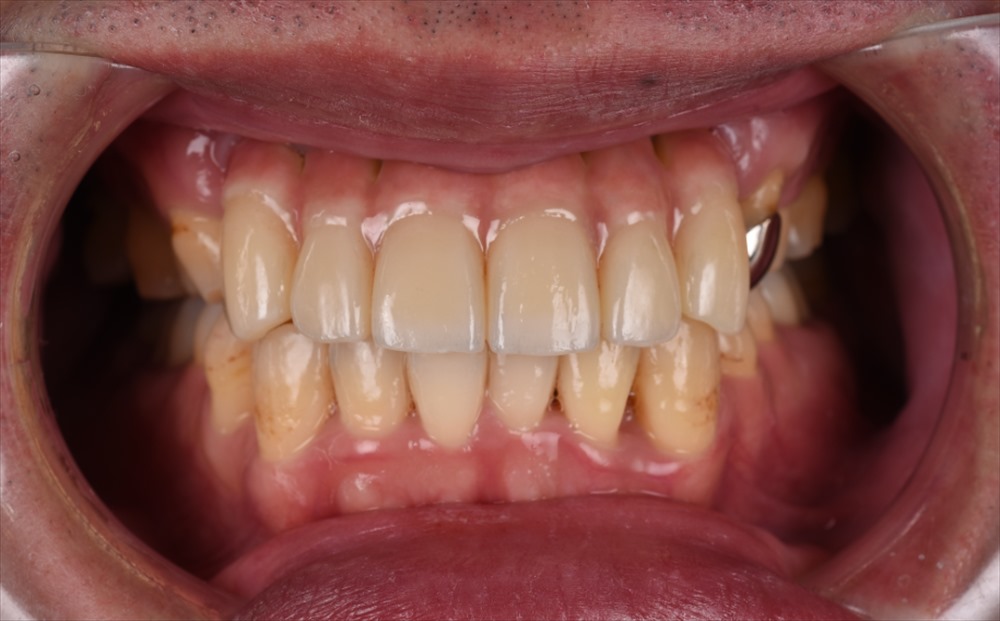

仮歯のコントロールをまた半年行い

本日

元々重度の歯周病とは誰も思わない歯肉です。

治療終了です。

元々お顔もスタイルもカッコ良い方なのですが益々カッコ良くなりました。

患者さまもとても喜んで頂き、なんだか今日のような日に歯科医を本気でやってて良かったと思います。